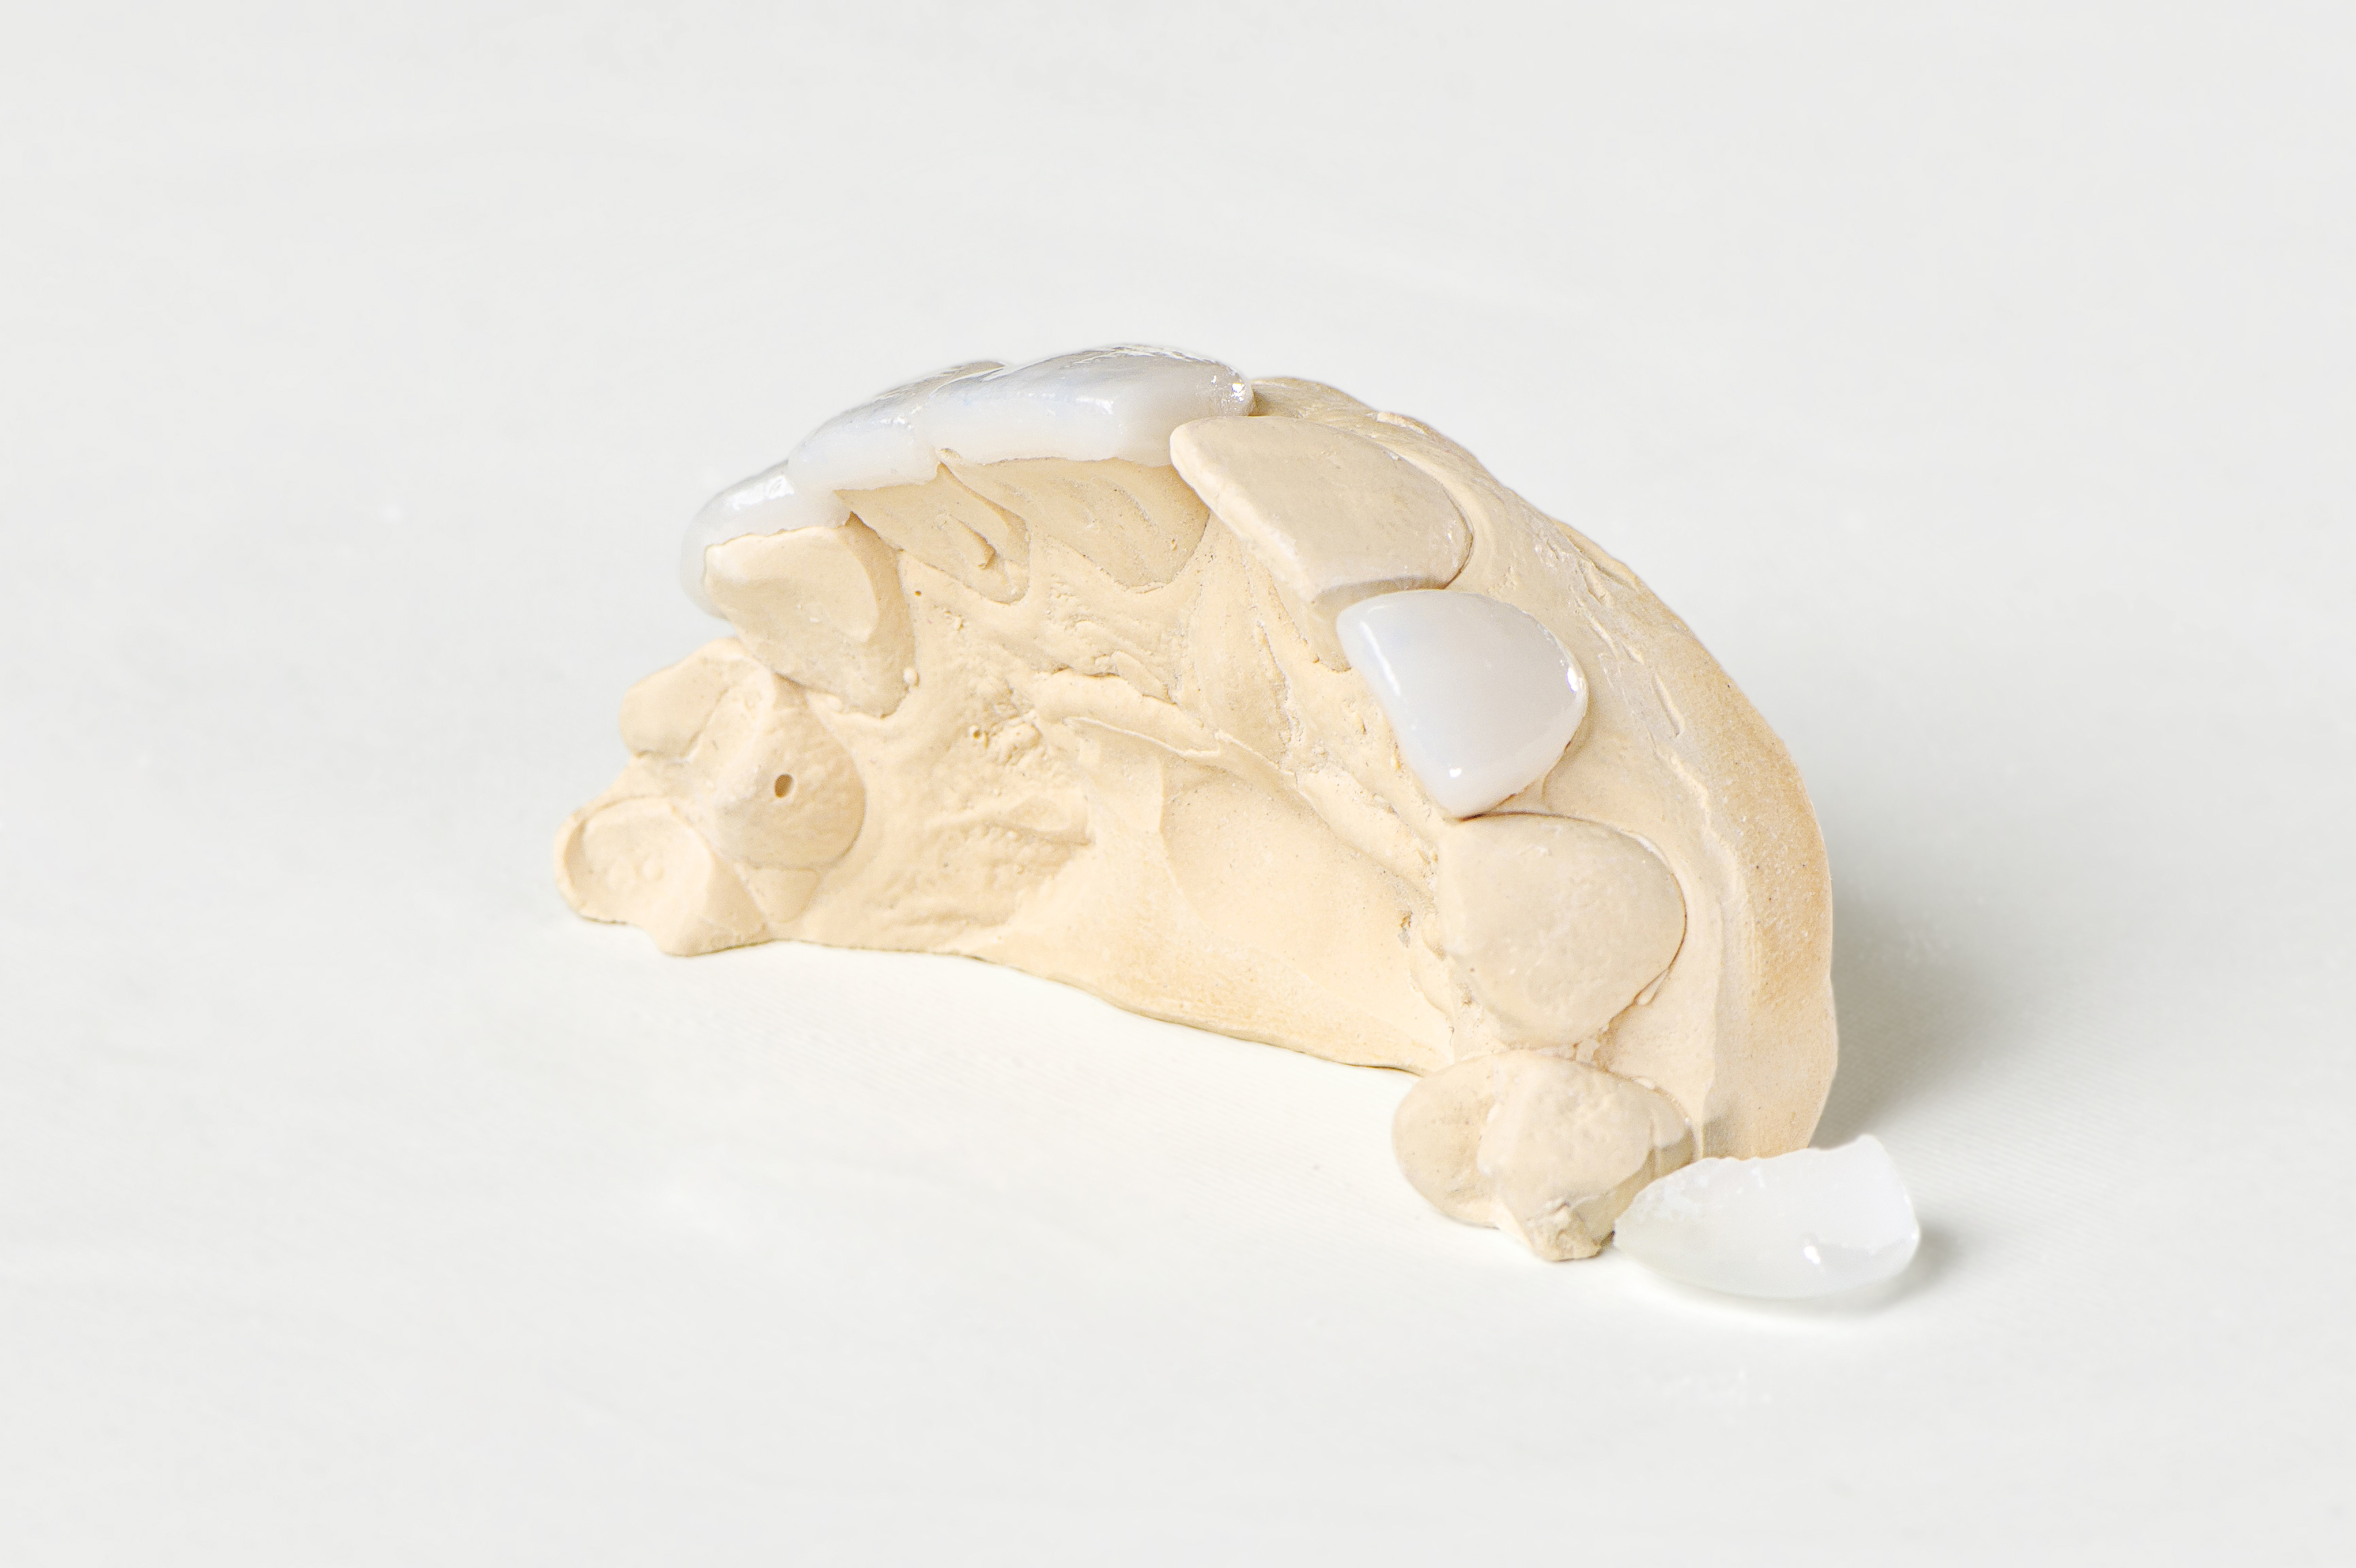

das variiert von Zahnarztpraxis zu Zahnarztpraxis. Wir schildern euch unseren Verlauf – am Beginn steht in der Regel eine Planungsphase – ein sogenanntes WaxUp. Es wird von deinen Zähnen ein Gipsmodell hergestellt, wo dann die Veneers aus Wachs angefertigt werden. So kannst du dir die Situation besser vorstellen. WaxUps werden vorallem dann hergestellt, wenn die Zahnstellung und die Zahnform stark verändert wird.

Am Ende der Präparation erfolgt der Zahnabdruck und die Bißnahme. Die provisorische Versorgung erfolgt mit Kunststoffveneers, diese werden unmittelbar nach dem Abdruck angefertigt. Der Zahntechniker benötigt ca. 3 Tage für die Herstellung der eigentlichen Veneers. Bei der Veneer Übergabe werden die Kunststoffprovisorien entfernt und die Zahnstümpfe gereinigt. Die Klebung kann mit und ohne lokal Anästhesie erfolgen. Nach dem Einsetzten der Veneers werden Kleberüberschüsse penibel entfernt und die Oberflächen poliert.

Wieviel und ob überhaupt etwas von der Zahnsubstanz entfernt werden muss, hängt von deiner Zahnstellung, deinen vorhandenen Zahnfüllungen und deiner Zahnfarbe ab. In der modernen Zahnheilkunde können Zähne durch solche minimal invasive Eingriffe korrigiert werden, Kronenbeschliffe sind nur mehr selten nötig – solch ästhetisch hoch anspruchsvolle Arbeiten erfordern aber ein gut eingespieltes Team (Zahnarzt, Zahntechniker und Assistentinnen). Aus diesem Grund haben wir die Zahntechnik, die Cad/Cam Fräßen und den 3D Drucker im eigenen Haus. Wir bilden den gesamten Zahnersatzfertigungsprozess im eigenen Haus ab, der ausführende Zahntechniker sieht zubeginn, während der Therapie und bei der Übergabe zu, er ist bei jeder Anprobe dabei und auch nach der Klebung sehen wir uns das Ergebnis gemeinsam an.